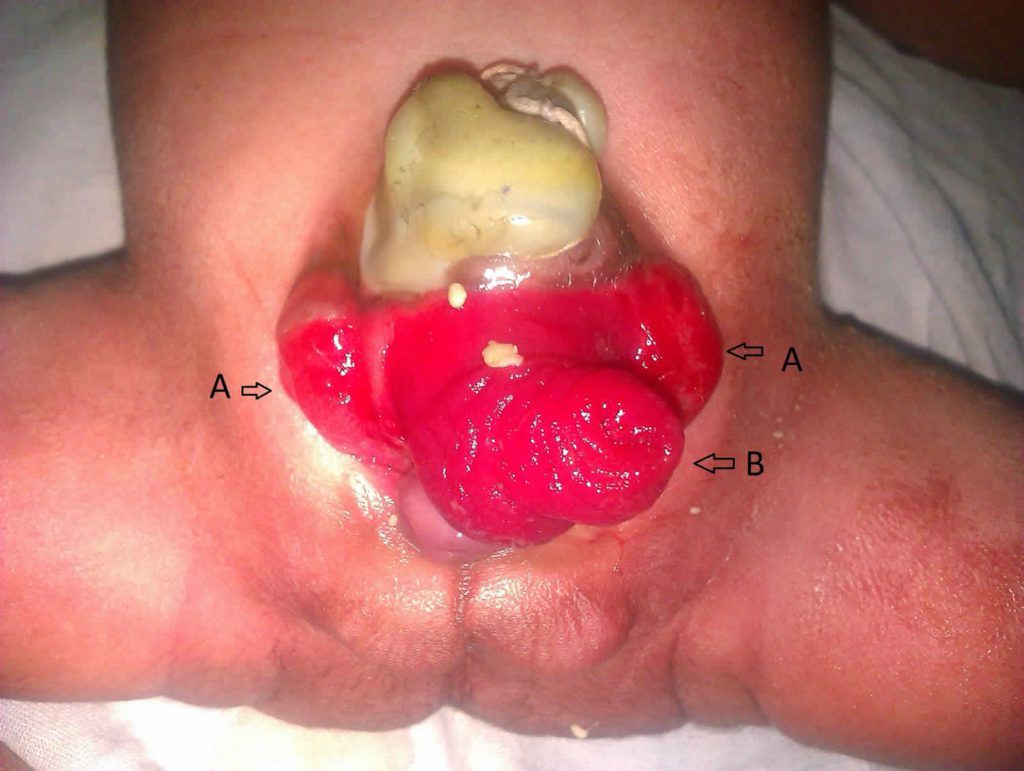

Bladder exstrophy is a rare congenital anomaly which develops as a result of abdominal wall defect. Bladder exstrophy is usually associated with other congenital anomalies such as imperforate anus, meningocele, and gastroschisis. Reference: https://healthjade.net/epispadias/ Image via: https://healthjade.net/epispadias/